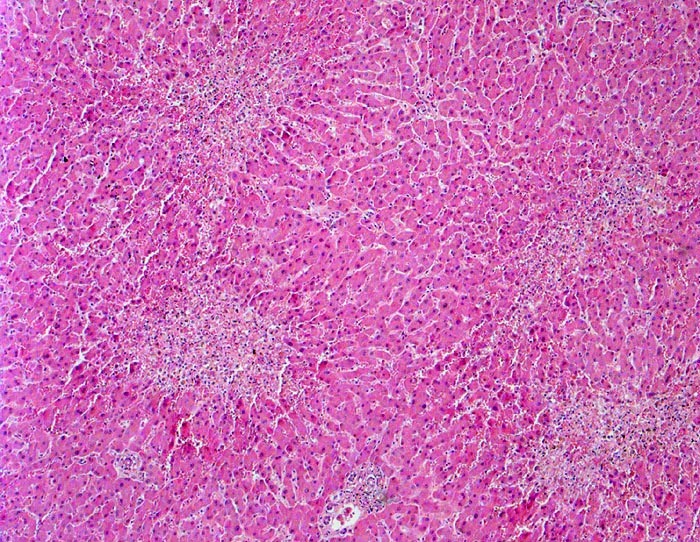

AP/ Perizentrale Schocknekrosen

Perizentrale Schocknekrosen

Linksherzversagen oder ein Schockzustand können zu einer hepatischen Minderperfusion mit ischämischen Koagulationsnekrosen der perivenulären Hepatozyten führen. Die Kombination von Hypoperfusion und retrograder Stauung (Rechtsherzversagen) führt zu zentrilobulären hämorrhagischen Nekrosen. Klinisch führen diese Nekrosen zu einer transienten geringen bis mässigen Erhöhung der Transaminasewerte, gelegentlich auch zu einem leichten Ikterus.

Metastasierendes Kolonkarzinom. Als Todesursache fanden sich nicht ganz frische zentrale und perizentrale Lungenembolien.